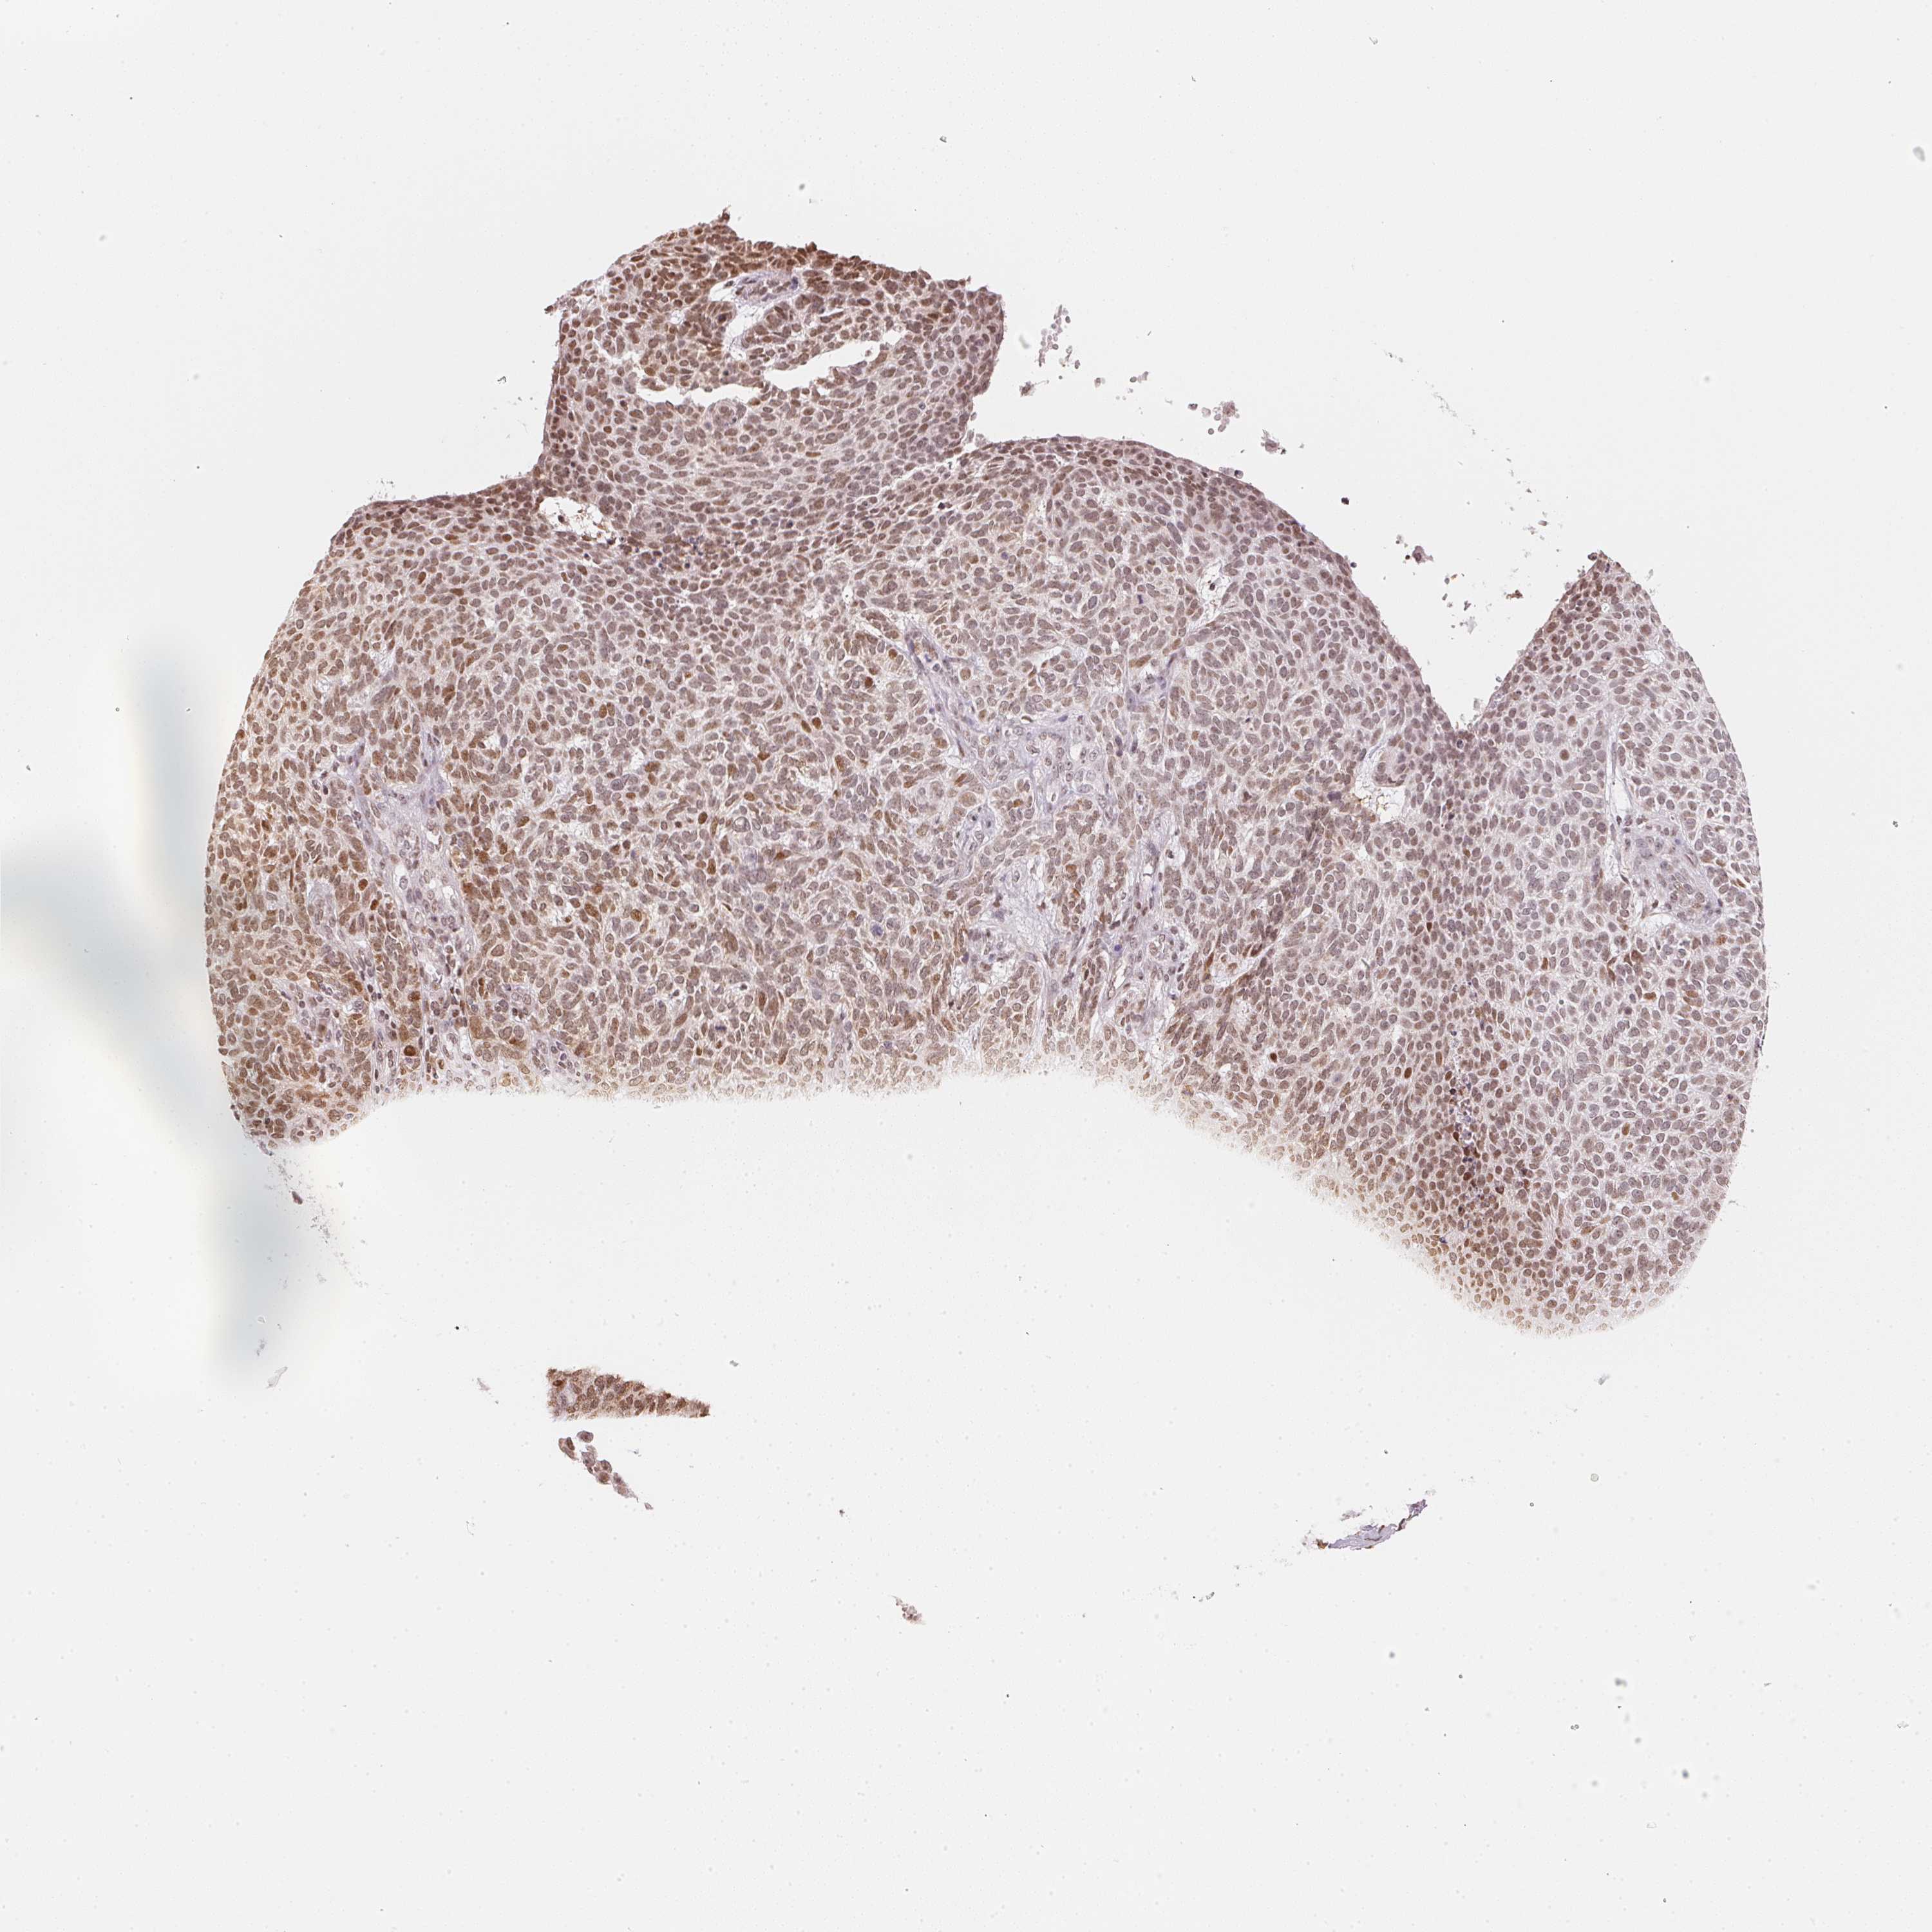

SKIN CANCER - Protein expressioni

A mouse-over function shows sample information and annotation data. Click on an image to view it in a full screen mode. Samples can be filtered based on level of antibody staining by selecting one or several of the following categories: high, medium, low and not detected. The assay and annotation is described here.

Antibody stainingi

Antibody staining in the annotated cell types in the current human tissue is reported as not detected, low, medium, or high, based on conventional immunohistochemistry profiling in selected tissues. This score is based on the combination of the staining intensity and fraction of stained cells.

Each image is clickable and will lead to virtual microscopy that enables deeper exploration of all samples and also displays staining intensity scores, fraction scores and subcellular localization as well as patient and tissue information for each sample.

Antibody HPA063266

Basal cell carcinoma